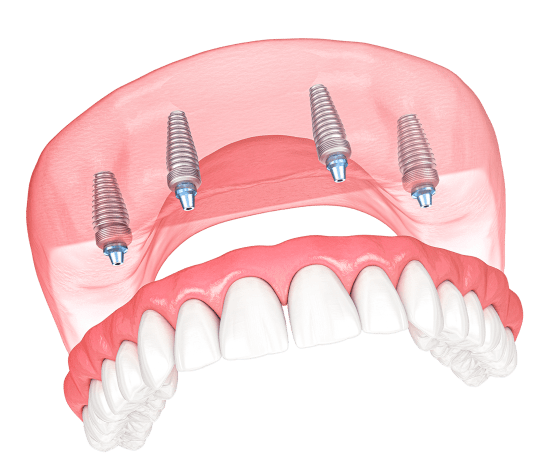

По уникальной методике

БЕЗ отёков и надрезов

Установка

за 1 день